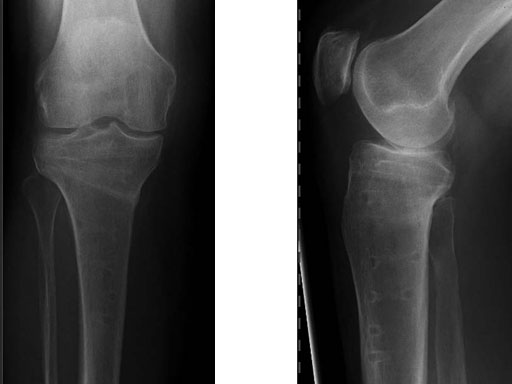

A 68-year-old female.

Case provided by Alex Staubli, Luzern, CH

The correction is planned on a long-leg standing x-ray. After surgery, the mechanical axis should pass through a point 63% on the lateral side of the total width of the tibial plateau in the frontal plane. A transverse or slightly oblique incision is used to avoid damage to the saphenous nerve. The distal fibers of the medial collateral ligament are detached from the tibia. Under fluoroscopic control, two wires are placed in the proximal tibia marking the transverse osteotomy plane. The cut usually starts at the upper margin of the pes anserinus and ends at the tip of the fibula on the lateral side. The wires are placed exactly parallel to the tibial plateau thus taking into consideration the individual tibial slope of the patient. An incomplete cut of the posterior two-thirds of the proximal tibia is performed with an oscillating saw guided by the wires. Continuous irrigation avoids burn injury to the bone. A second osteotomy is now performed in the anterior third of the tibia in an angle of 100 ending above the patellar tendon insertion. A smaller saw blade is used and the complete anterior cortex is cut exactly in the frontal plane. The osteotomy is now gradually opened by inserting flat chisels or a spreader-chisel into the posterior osteotomy cleft. This process may take some minutes and can usually be completed without fracture of the lateral cortex. A bone spreader is now placed in the posteromedial edge of the tibia and the chisels are removed. The leg is extended and the correction is checked with the fluoroscope. A long metal rod is placed between center of the hip joint and center of the ankle joint. The projection of this rod should be at the planned point of correction on the tibial plateau lateral of the midline. Eccentric collapse of the medial joint space may cause accidental overcorrection. In this case pressure on the foot may simulate loading and body weight. The correction can be fine-tuned by opening or closing the spreader. The TomoFix Medial Tibia Plate is now placed in a subcutaneous pocket. The implant is precontoured and usually fits well to the bone surface. The distance holders avoid compression of the medial collateral ligament and the pes anserinus. Three proximal bolts are placed near the subchondral sclerosis zone. The position of the bolts is adapted to the anatomy of the proximal tibia giving optimum purchase for the bolts. An oblique lag screw is inserted distal to the osteotomy. This screw in the first combination hole allows careful compression of the lateral osteotomy hinge and pretensioning of the implant. A stab incision is created on the shaft and the implant is fixed monocortically with bolts. The lag screw and the distance holders are replaced by bolts. The medial collateral ligament is released longitudinally to reduce medial compartment pressure and the wound is closed in layers. An overflow drain may be used. Clinical and experimental work has proven that when this technique is closely followed, corrections up to and over 15 mm can be performed without bone grafting or use of bone substitutes.